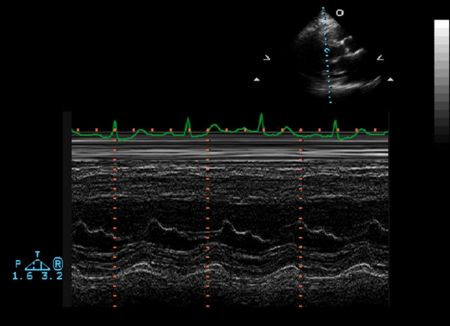

M mode echocardiography

A single crystal rapidly alternates between transmission and receiver modes with rapid updating result, rapidly moving structures (eg, valve leaflets) can be monitored for their characteristic motion very high temporal resolution

Ventricular M-mode